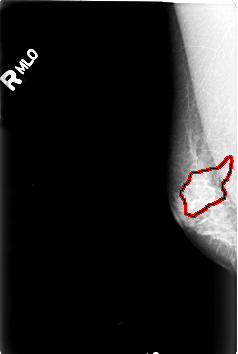

B_3003_1.RIGHT_MLO

RIGHT_MLO LINES 4592 PIXELS_PER_LINE 3088 BITS_PER_PIXEL 12 RESOLUTION 50 OVERLAY

FILE: B_3003_1.RIGHT_MLO.OVERLAY

TOTAL_ABNORMALITIES 1

ABNORMALITY 1

LESION_TYPE CALCIFICATION TYPE FINE_LINEAR_BRANCHING DISTRIBUTION SEGMENTAL

ASSESSMENT 5

SUBTLETY 3

PATHOLOGY MALIGNANT

TOTAL_OUTLINES 1

BOUNDARY